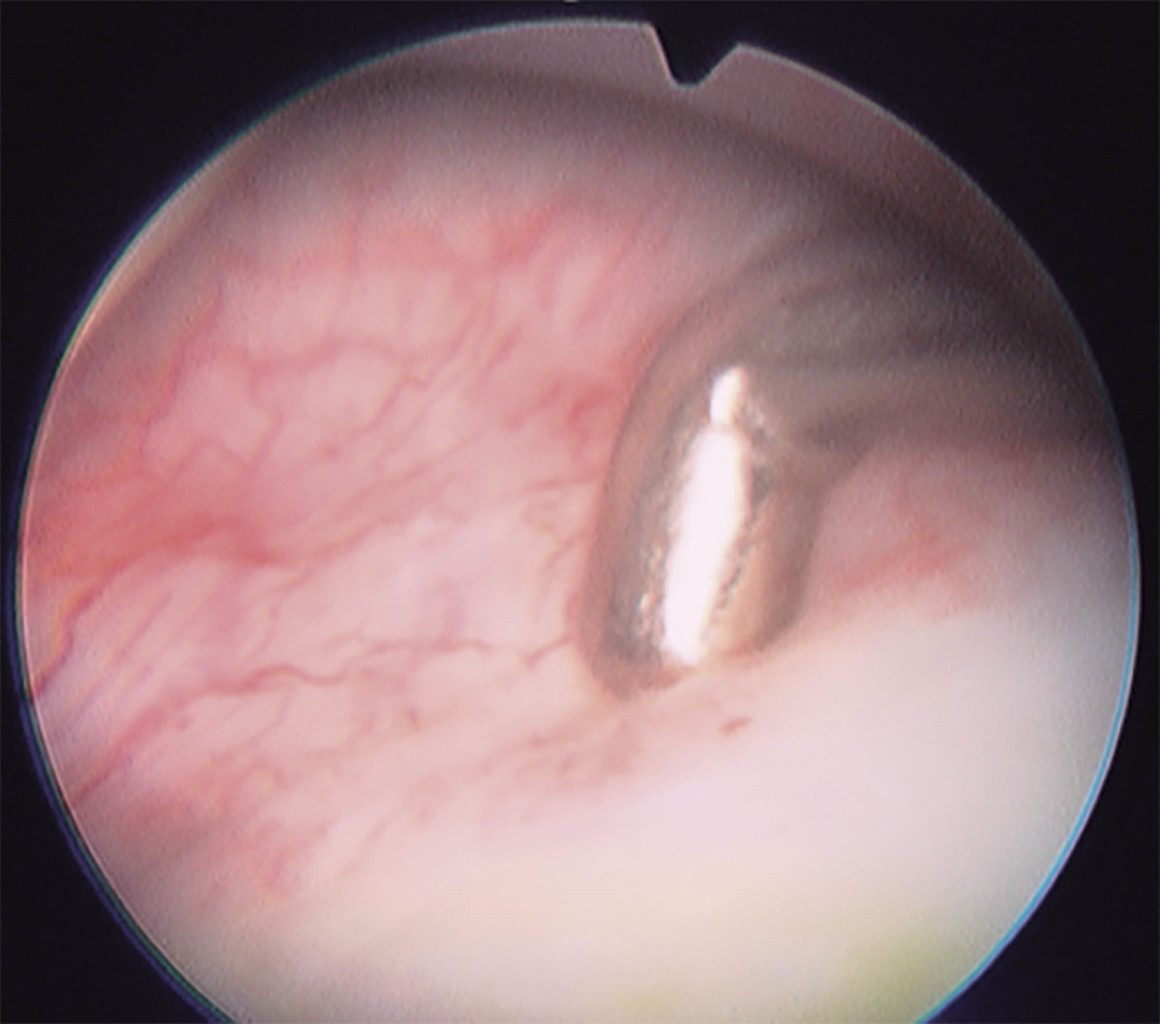

Temporomandibular joint disorders (TMD) in any of its modalities, such as disc displacement with or without reduction, unstable discs, disc perforations, chronic synovitis (Figure 1) or the final stages such as osteoarthrosis, are among the most common problems in the daily consultation of the maxillofacial surgeon.

At this point, the diagnosis of the posterior recess is carried out, with the bilaminar zone (Figure 10), the auditory canal afterwards, anteriorly the mandibular condyle, with its transition between the bilaminar zone and the disc, as well as medially the pterygoid shadow.14